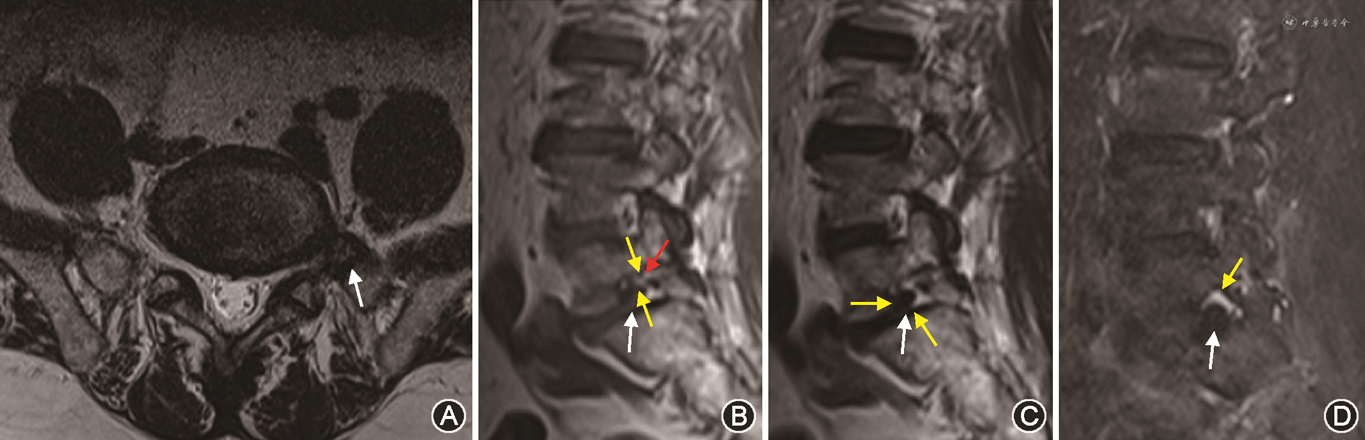

2. 改良系统:83例患者中,评估为0级的有3例,其中保守组3例,手术组无病例,MRI表现为椎间孔无狭窄,神经根周围无脂肪闭塞;评估为1级的有19例,其中保守组18例,手术组1例,MRI表现为椎间孔轻度狭窄,神经根无明显形态学改变,神经根周围脂肪闭塞小于神经根周长的50 %(图2);评估为2级者14例,其中保守组13例,手术组1例,MRI表现为椎间孔中度狭窄,神经根无明显形态学改变,神经根周围脂肪闭塞大于神经根周长的50 %;评估为3级者47例,其中保守组15例,手术组32例,MRI表现为椎间孔重度狭窄,清晰显示神经根被挤压在椎间孔上壁并明显变细或塌陷(图3、4,表1)。

多项研究认为T1WI序列神经根周围脂肪闭塞程度是对IFS程度最具提示意义的指征[5, 6, 7, 8],应用最广泛的是Lee系统[7, 8, 9, 10]。本研究发现,Lee系统对常为偏心性狭窄的FLDH-IFS分级有很大的缺陷,如对神经根周围有1个方向脂肪闭塞者(0~1级之间者)不能准确地分级,既可以评估为0级也可以评估为1级,同样对神经根周围有3个方向脂肪闭塞者(1~2级之间者)也不能准确地分级,既可以评估为1级也可以评估为2级,导致评估者很难做出一致准确的判断,可重复性低。本研究结果显示两种系统评级结果之间差异具有统计学意义,改良系统优于Lee系统,改良系统的观察一致性也明显高于Lee系统。Lee系统的0~3级之间部分(0~1级之间、1级、1~2级之间、2级)由改良系统合理有效地衔接、整合为2个级别(神经根周围脂肪闭塞小于神经根周长50 %的1级和大于50 %的2级),能够全面、准确地分级。并且在Lee分级系统中,神经根受压情况常不能清晰显示,而改良系统增加了T2WI-FS序列,能够清晰、准确地显示高信号神经根的位置(如神经根被挤压在椎间孔上壁)、大小(如明显变细)、形态(如形态学改变、塌陷),从而能够准确地分级。改良系统对这些影像学表现特点的评估,明显优于Lee系统。

治疗前MRI图像的准确分级对治疗的成功非常重要[18]。本研究结果进一步表明,两种分级系统均为评级越低,临床上越倾向于选择保守治疗,评级越高,临床上越倾向于手术治疗,但改良系统的这种倾向比Lee系统更加明确。改良系统的评级与治疗方式之间的相关性明显高于Lee系统。两种系统行保守治疗有效的非3级(0~2级)百分比分别为94.6 %(139/147)、64.2 %(170/265),需要手术治疗的3级百分比分别为69.2 %(128/185)、61.2 %(41/67)。可见改良系统明显优于Lee系统,能使所评级的绝大多数非3级患者行保守治疗有效,从而避免过度的手术治疗和无效的保守治疗,有助于临床医师制定合理的治疗方案。

T2WI-FS序列显示神经根受压程度最清晰,所以快速而准确的评估方法是先看T2WI-FS序列。如果神经根明显被挤压在椎间孔上壁并明显变细或塌陷时就属于3级;如果神经根没有明显形态学改变时,再看T1WI、T2WI显示神经根周围脂肪闭塞的程度。若神经根周围脂肪闭塞大于神经根周长的50%时为2级,若神经根周围脂肪闭塞小于神经根周长的50 %时为1级,若神经根周围没有脂肪闭塞时为0级。改良系统特别是对较重的2、3级患者能够准确地分级,因为这个分级不是取决于椎间孔内神经根周围脂肪闭塞方向的个数,而是取决于椎间孔内神经根周围脂肪闭塞占神经根的周长比。